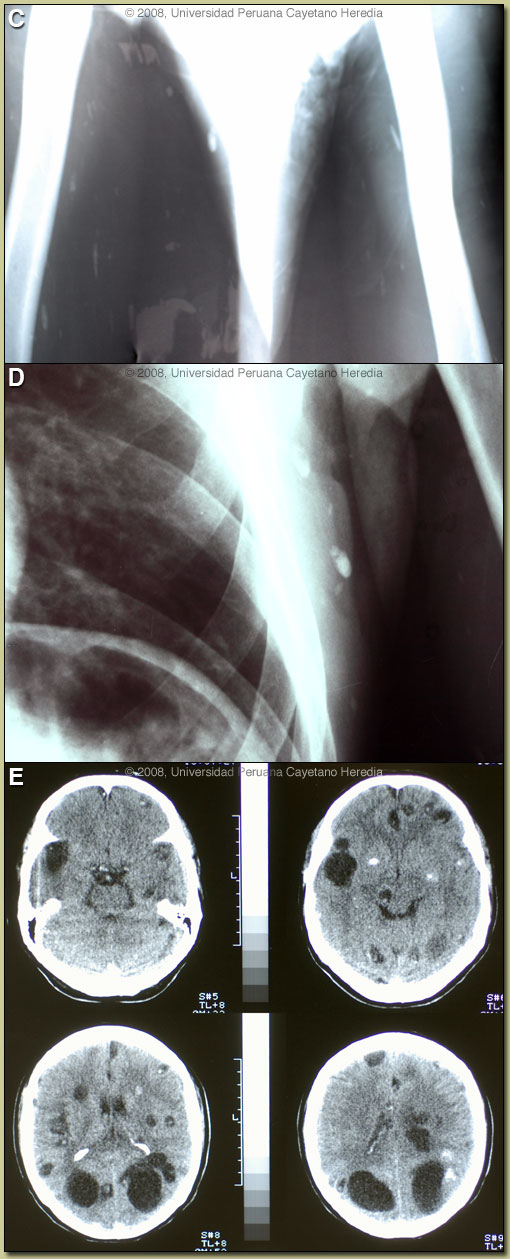

| Diagnosis: Neurocysticercosis due to Taenia solium. Cysticerci in soft tissue. |

A CT scan of the head [Image E] showed a total of 35 lesions in different stages of evolution, including calcified lesions as well as several very large lesions that are bigger than the typical 1-2 cm lesions associated with viable cysts. In this case, these large cysts are (or at least act as) parenchymal cysts. With some frequency cysts in the Sylvian fissure (those which become very large) are actually subarachnoid in nature but behave as parenchymal: seizures, some mass effect with minimal CSF inflammation and usually respond to antiparasitic drugs. Other examples of such large lesions may be found at [http://tmcr.usuhs.mil/tmcr/chapter7/clinical7.htm]. No intraventricular lesions or signs of intracranial hypertension were seen in this patient. Edema around a dying cyst is often the trigger for onset of seizures in infected individuals. Cysticercosis is infection with the larval stages of the human pork tapeworm Taenia solium. Humans acquire cysticercosis after ingesting eggs of T. solium in material contaminated with feces originating in human tapeworm carriers. Humans that do not eat pork can get cysticercosis. Ingestion of contaminated pork results in humans getting an adult intestinal tapeworm not cysticercosis. Cysticercosis is common in many developing countries and very common in rural agricultural areas of Perú. In developed countries the long-lived cysticerci are increasingly seen as immigration from affected areas rises. Occasional transmission by tapeworm carriers to those who have never left non-endemic countries is reported. Ingested T. solium eggs hatch in the stomach and are then carried to the muscles and other tissues where the larvae encyst and reach their usual size of about 1 cm within a few months. Clinical manifestations depend on the affected organ but neurocysticercosis causes the most morbidity. The cysticerci seem able to evade the immune system and are thought to remain viable for several years without causing any inflammatory response. Most clinical symptoms are the direct result of inflammatory responses that accompany the eventual cyst degeneration. Epileptic seizures are the primary or sole clinical manifestation in up to 80% of patients. In endemic regions new onset seizures in teenagers or young adults is most likely due to neurocysticercosis. Cysticerci can also cause symptoms because of mass effect, impingement on a vital structure, or blockage of CSF circulation especially if the cyst is intraventricular. In all cysticercosis patients, seizures need to be managed as per any other form of epilepsy. Treatment of parenchymal neurocysticercosis with antiparasitic drugs such as albendazole is increasingly accepted even when there are few lesions. Albendazole clearly kills the cysts, but may lead to added inflammation and exacerbation of symptoms, which is usually dealt with by empiric concomitant use of steroids. Therapeutic decisions should be based on the number, location, and viability of the cysts. Patients in whom all lesions are already calcified should receive no anti-parasitic treatment. Recent work indicates that long-standing calcified lesions can sometimes provoke peri-lesional edema, which may need treatment with steroids as well as anti-seizure medication. Special considerations apply to patients such as this with large numbers of active lesions due to the chance to induce a diffuse encephalitis due to the severe inflammation due to simultaneous killing of many organisms. Intraventricular shunting may be necessary if intracranial hypertension results from treatment. Neurocysticercosis is a variable disease and treatment approaches need to be individualized to a large number of differing clinical presentations [Neurology. 2006 Oct 10;67(7):1120-7]. Our patient elected treatment with prolonged albendazole for 30 days under steroid cover and anti-seizure medication. In our experience (no controlled data) large cysts do better with treatment longer than the standard 8 days. He has tolerated the first 10 days of therapy without incident and the subcutaneous nodules have shrunk in size. Steroid management in these cases (when you have to maintain it for a long time) is a problem. The idea is to try to decrease doses as soon as possible after the second week of treatment realizing that the attempt may not be immediately successful.